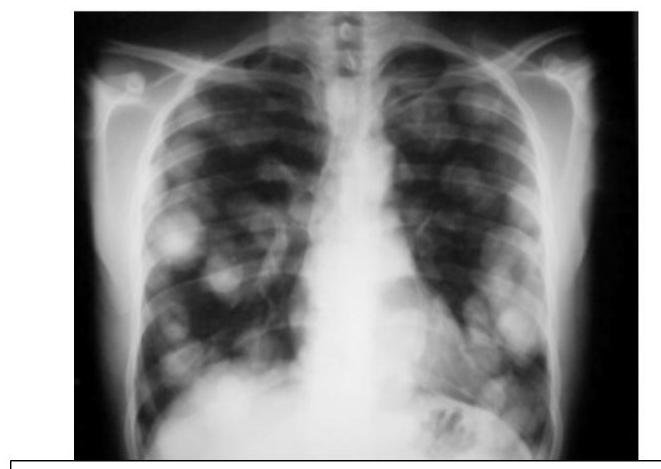

# CÁNCER DE PULMÓN ## DEFINICIÓN Se considera el tipo **Células No Pequeñas** el **cáncer de pulmón** más frecuente; este es una **neoplasia maligna** originada en el **epitelio** que recubre el **aparato respiratorio** (bronquios, bronquiolos y alvéolos) y representa el 80 % de todos los casos de cáncer de pulmón. La OMS divide el cáncer de pulmón en dos clases basadas en su biología, tratamiento y pronóstico: ## 1. CÁNCER PULMONAR DE CÉLULAS NO PEQUEÑAS a. No ESCAMOSO (Adenocarcinoma, Carcinoma de Células Grandes) b. Escamoso (EPIDERMOIDE) 2. CÁNCER PULMONAR DE CÉLULAS PEQUEÑAS ## CÁNCER PULMONAR MÁS COMÚN: ADENOCARCINOMA ## EPIDEMIOLOGÍA - Es la primera causa de muerte en el mundo (hombres) y segunda de mujeres. - Alrededor del 18-25% de muertes en todos los cánceres. - Tumor más letal - Tasa de letalidad: 84 % - Más frecuente en hombres. - Variantes según estatus socioeconómico (tipo de cigarrillos, exposición laboral o agentes inhalados). ## FACTORES DE RIESGO: - Tabaquismo activo: 85% - Tabaquismo pasivo: 5% - ÍNDICE TABÁQUICO >20 PAQUETES/AÑO - Radón - Asbesto - Radiación - Níquel - Cromo Factores que influyen en el tabaquismo: - Duración del tabaquismo - Número de cigarrillos - Inicio a edad más temprana - Predisposición genética TABAQUISMO TOTAL: 95% ÍNDICE TABÁQUICO Número de cigarrillos/día x Número de años que lleva fumando 20 ## Tabaquismo pasivo: - Riesgo relativo: 1.24 - Causante del 25-30% de los cánceres de pulmón en no fumadores. - 30 % de la población general está expuesta al humo pasivo. - Vivir con un fumador: Incrementa el riesgo 30% de cáncer pulmonar. # DETECCIÓN Y TAMIZAJE Se recomienda el uso de un protocolo basado en tomografías de tórax de baja dosis anual como herramienta de detección oportuna en pacientes con: 1. Índice tabáquico igual o mayor a 30 cajetillas/año 2. Edad 55-74 años Incorporar programas de deshabituación al tabaquismo para disminuir el costo-efectividad y mejorar los programas de detección oportuna. Las características clínicas y radiológicas no pueden distinguir entre nódulos benignos y malignos, aunque es importante estimar la probabilidad clínica de malignidad antes de indicar estudio de imagen: ## PROBABILIDAD MALIGNA BAJA (<5 %) Nódulo sólido indeterminado +8 mm con los siguientes factores: - Paciente joven - Bajo consumo de tabaco - Nódulo de tamaño pequeño - Localización no superior - Resolución completa o casi completa - Disminución progresiva o persistente - Sin crecimiento en los últimos 2 años (en nódulos sólidos) - Sin crecimiento en los últimos 3-5 años (en nódulos subsólidos) ## PROBABILIDAD MALIGNA ALTA (+65 %) Nódulo sólido indeterminado +8 mm con los siguientes factores: - Edad avanzada - Alto consumo de tabaco - Historia de cáncer previa - Nódulo de gran tamaño - Nódulo con márgenes irregulares - Localización en lóbulos superiores - Evidencia de crecimiento en estudios de imagen # CLÍNICA Es un cuadro insidioso que no produce síntomas hasta que la enfermedad está avanzada. En aproximadamente el 10 % de los casos, el cáncer pulmonar se diagnostica en pacientes asintomáticos cuando se realiza una radiografía (Rx) de tórax por otro motivo. ## SIGNOS Y SÍNTOMAS MÁS FRECUENTES 1. Tos (8-75 %) 2. Dolor torácico (20-49 %) 3. Disnea (3-60 %) 4. Hemoptisis (6-35 %) 5. Astenia (0-10 %) 6. Pérdida de peso (0-68 %) 7. Anorexia (0-20 %) 8. Acropaquia (0-20 %) 9. Fiebre (0-20 %) ## Al diagnóstico: - 20 % enfermedad aislada - 25 % metástasis regionales - 55 % metástasis a distancia ## SÍNDROMES PARANEOPLÁSICOS ## TUMOR DE PANCOAST Es un tumor del surco superior (región apical torácica) que afecta la estructura de la pared torácica apical a nivel de la primera costilla superior, pero no necesariamente tiene un síndrome de Horner o dolor irradiado hacia el brazo; presenta dolor de hombro. Frecuentemente invade el plexo braquial, vasos subclavios o médula. - Asociado a síndrome de Horner: ptosis + miosis + anhidrosis ## METABÓLICOS  - Hipercalcemia: asociada a metástasis óseas, asociada a producción ectópica de hormona paratiroidea. - Síndrome de Cushing: producción excesiva de corticotropina, con exceso de producción de cortisol que causa debilidad muscular, pérdida de peso, hipertensión, hiperglucemia e hipocalemia severa. - común en cáncer de células pequeñas.  # DIAGNÓSTICO Para un diagnóstico preciso y estadificación se requiere un abordaje completo con el fin de evaluar la extensión de la enfermedad y realizar lo siguiente: General: Historia clínica, exploración física, evaluación de comorbilidades y capacidad funcional. ## Imagen: - Radiografía de tórax: se recomienda en todas las sospechas de cáncer pulmonar. - Si hay nódulo sospechoso (+8 mm) \rightarrow TAC de alta resolución. - TAC helicoidal de tórax: se recomienda contrastada y de abdomen ante la sospecha, independientemente de la radiografía (Rx). - Tomografía por emisión de positrones (PET-CT): importante marcador diagnóstico y de planificación del tratamiento (Tx). - RMN: recomendada para evaluación quirúrgica de los estadios T4 N1. Laboratorio: BH, función renal, enzimas hepáticas y metabolismo óseo. Función cardiopulmonar: EKG, espirometría, capacidad de difusión pulmonar de monóxido de carbono. Obtención de tejido: broncoscopia, USG endoscópico bronquial, biopsia guiada por TAC.   PATRÓN metastásico con imagen en "suelta de globos", con apariencia algodonosa. # TOMA DE BIOPSIA ## CITOLOGÍA DE ESPUTO - Método útil para diagnóstico y no invasivo. - Ante un resultado negativo, se deberá continuar con otras pruebas. - Sensibilidad variable dependiendo del tumor y del procesamiento. ## BRONCOSCOPIA - Es la prueba recomendada para obtener una muestra diagnóstica por biopsia de cualquier lesión visible. - El uso de técnicas avanzadas (USG endobronquial) debe considerarse en tumores donde los métodos tradicionales han fallado para la obtención de material. ## BIOPSIA POR ASPIRACIÓN CON AGUJA FINA GUIADA POR USG - Es la primera elección para el diagnóstico patológico en nódulos sospechosos. ## MEDIASTINOSCOPIA - Es la prueba con el valor predictivo negativo más alto para descartar enfermedad en ganglios. - No es necesaria en estadios clínicos tempranos IA, sin crecimiento ganglionar y en caso de que el PET-CT no muestre captación ganglionar mediastínica. - Se indicará si las pruebas menos invasivas no son accesibles, valorables o insatisfactorias. # CÁNCER PULMONAR DE CÉLULAS NO PEQUEÑAS ## CARCINOMA ESCAMOSO (EPIDERMOIDE) - Localización: CENTRAL - Asociado al tabaco. Liberación de hormona paratiroidea  TUMORES CARCINOIDES / CARCINOMA DE CÉLULAS GRANDES  PUEDEN CRECER EN CUALQUIER PARTE DEL PARÉNQUIMA. # TRATAMIENTO ## Etapa clínica I - Resección quirúrgica - Adyuvancia con QT si hay factores de riesgo - Si N+ - radioterapia ## Etapa clínica II y III - Quimiorradioterapia - Inmunoterapia ## Etapa clínica IV - Tratamiento sistémico - Quimioterapia (base de platino) - Terapia dirigida - Inmunoterapia - Metástasis única en SNC - radioqx - Metástasis única en SNC - radioterapia, radioqx